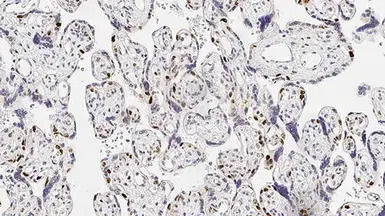

IHC-P analysis of human placenta tissue using GTX01862 p57 Kip2 antibody [25B2]. Note nuclear staining for cytotrophoblast and stromal cells of the villi.